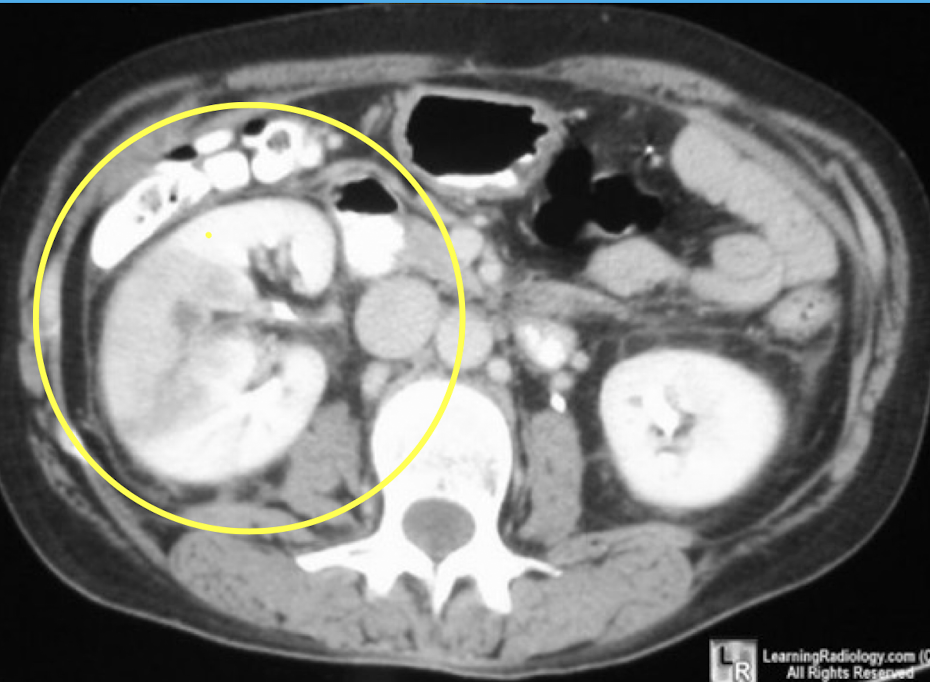

Pyelonephritis

CT Abdomen/Pelvis IV contrast

Renal cell carcinoma

CT Abdomen/Pelvis IV contrast